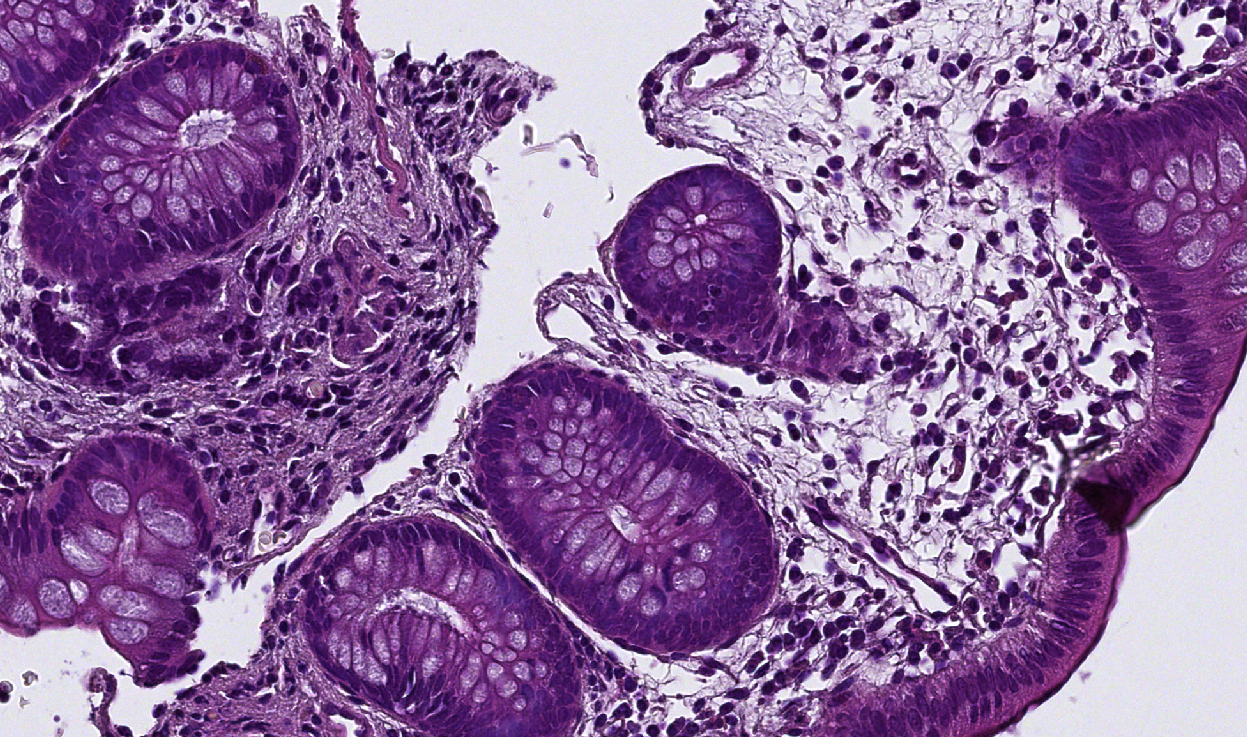

| Original image | Empty / chaotic | Interesting |

|---|---|---|

![]() |